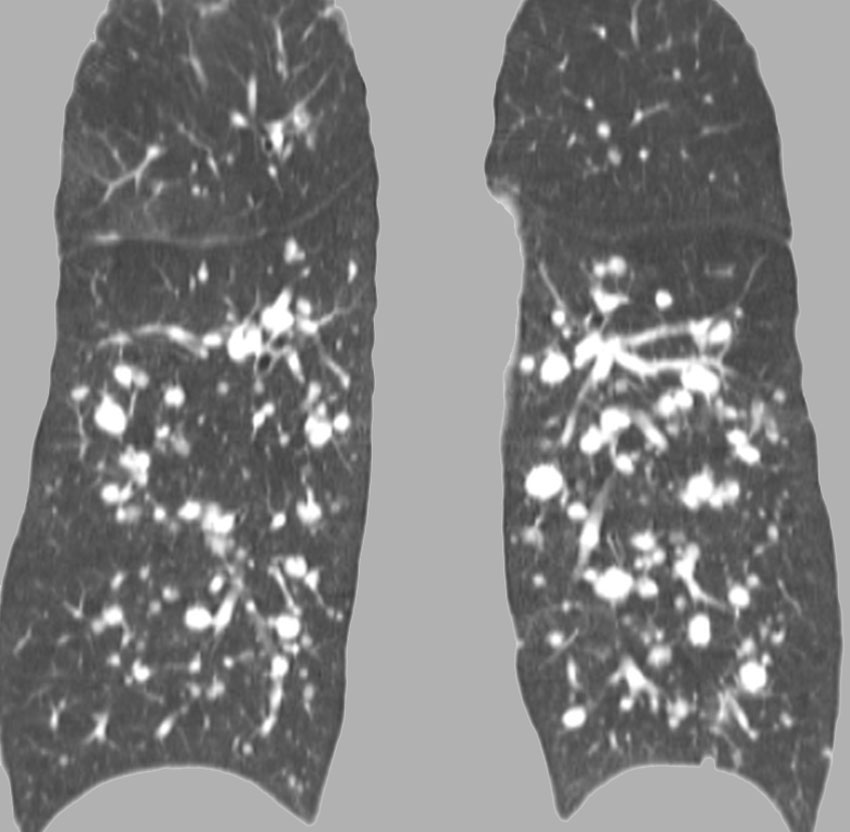

- でもきわめてまれに,頸静脈を介して肺転移します

- 髄膜腫の肺転移と同じような,ゆっくりとした進行という予後となります

- これは頸静脈を介してのこぼれ落ちるような肺転移です

- ですから,頸静脈を遮断するような腫瘍摘出手術をすれば予防できるという考え方もあります

多発性肺転移が発見され無治療で14年が経過しました。肺転移巣は無数ですがたいして増大しませんので普通の生活ができています。